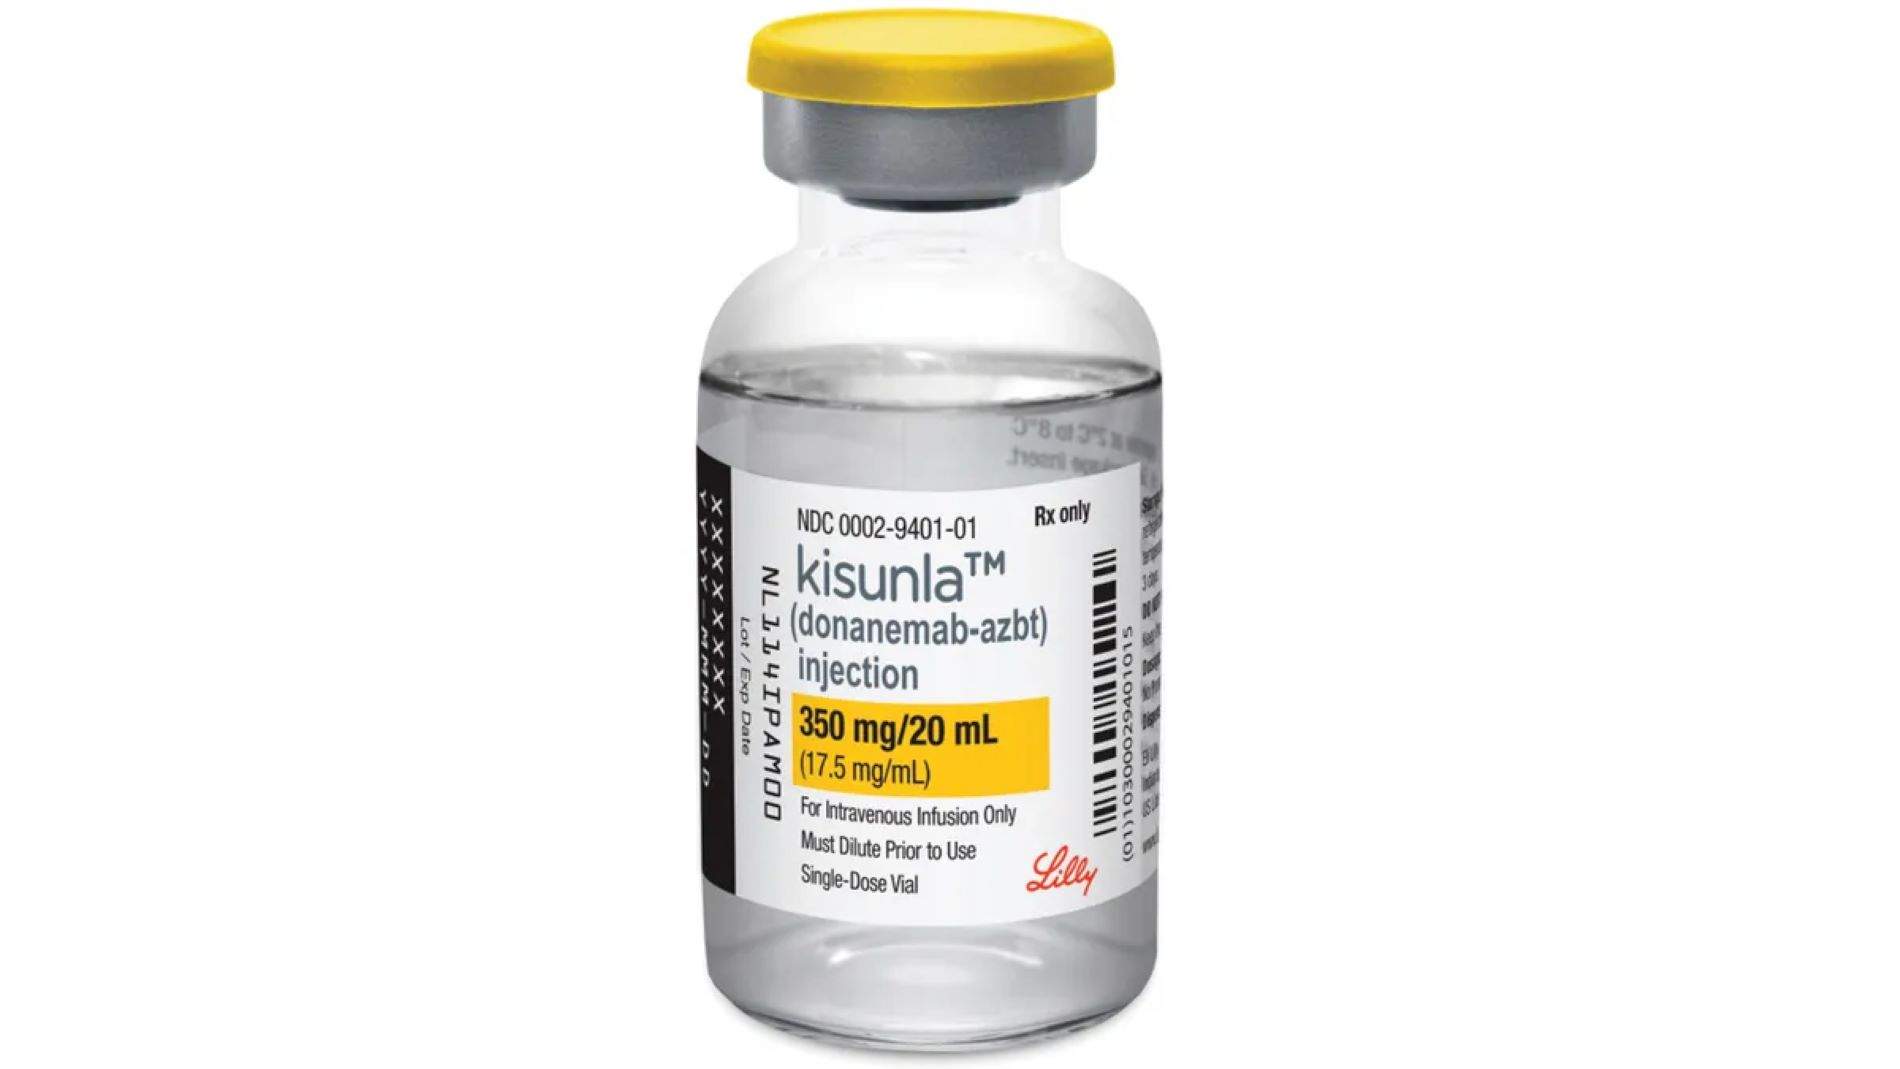

La EMA rechaza la licencia para Kisunla, una inyección pensada para tratar al Alzhéimer en etapas tempranas